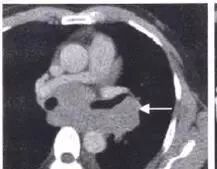

肺门肿块,肿块侵入支气管,鳞癌。假如出现阻塞性肺炎,更支持鳞癌